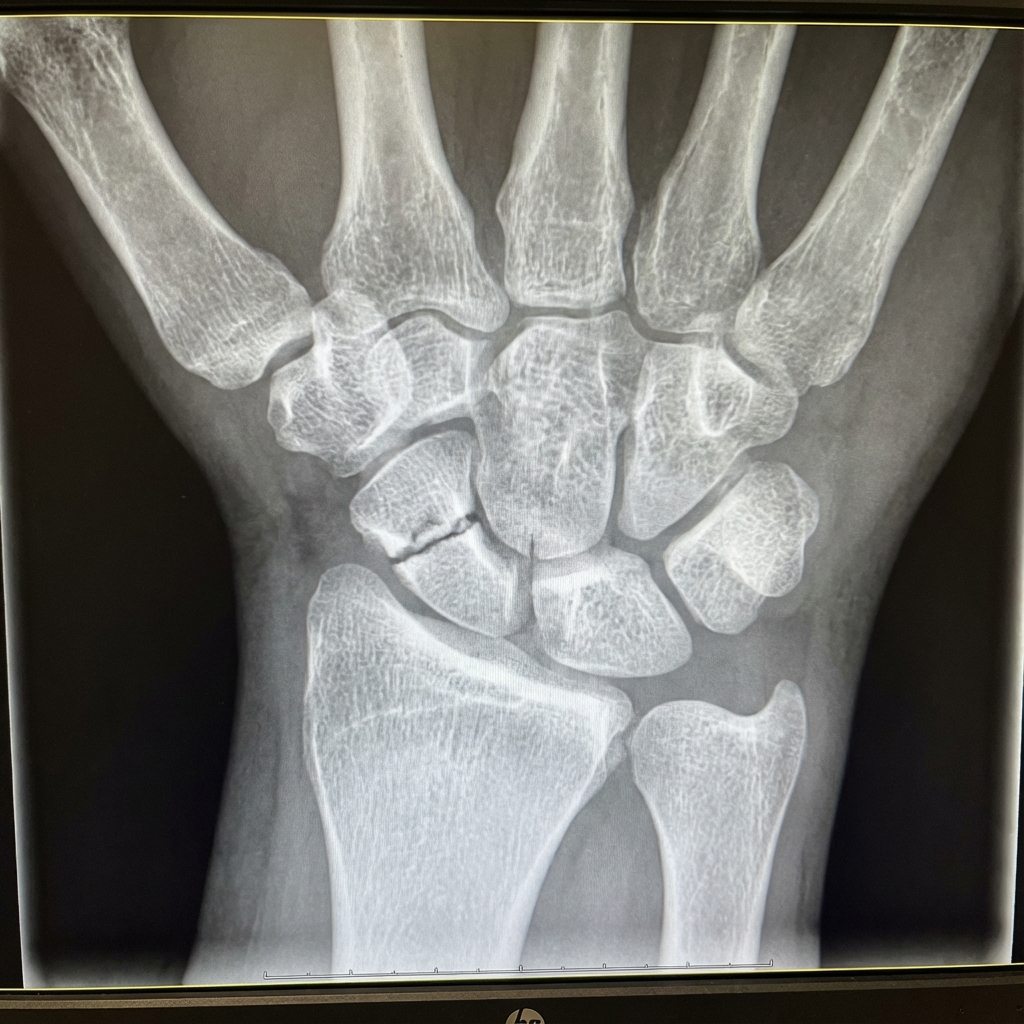

PA wrist radiograph with scaphoid (ulnar deviation) view demonstrating a displaced scaphoid waist fracture. There is >1mm displacement and >15° humpback deformity. The fracture line is clearly visible across the waist. No secondary arthritis is present. This fracture pattern has increased non-union risk and requires surgical fixation with headless compression screw.

Source: Educational radiograph of a displaced scaphoid waist fracture • OrthoVellum Medical Education Team • OrthoVellum Educational Use